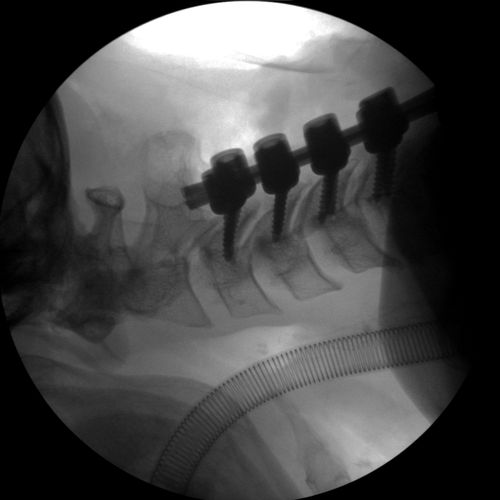

Cervical Spine Fixation